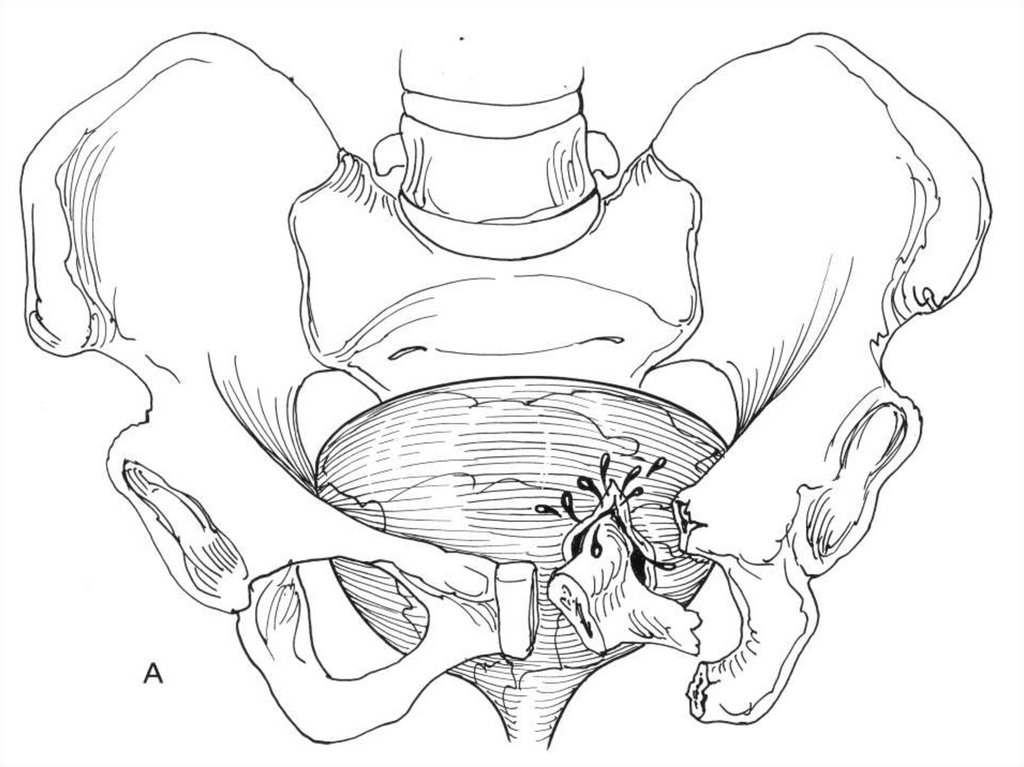

СТЕПЕНИ ТЯЖЕСТИ ТРАВМ ПОЧКИ (ААХТ)

• 1 ст.: Ушиб или не распространяющаяся

подкапсульная гематома, разрыва нет;

• 2 ст.: Не распространяющаяся

паранефральная гематома, разрыв